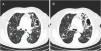

En busca de la aspergilosis

In search for aspergillosis